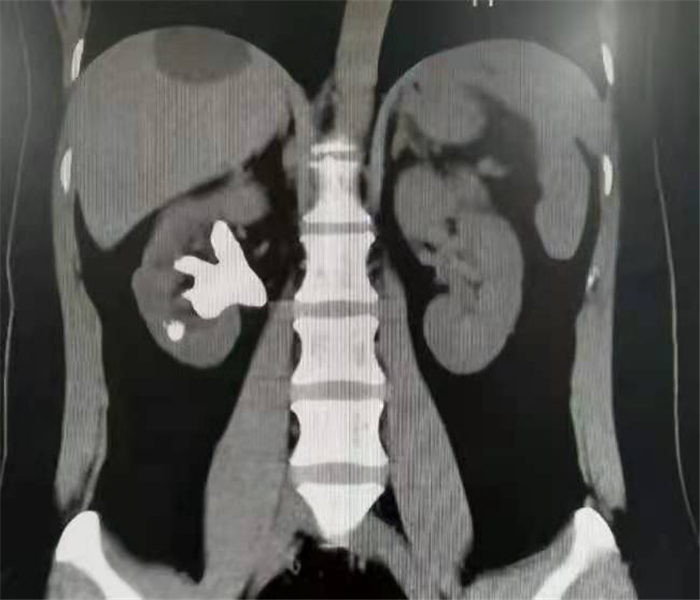

肾脏是血管非常丰富的器官,血流占心脏排出血量的1/4。经皮肾镜碎石取石术(英文简写为PCNL),就是在患者腰部建立一条从皮肤到肾脏的通道,通过这个通道把肾镜插入肾脏,利用激光、超声等碎石工具,把肾结石击碎取出,通俗来说就是“打孔取石”。

“打孔取石”既要尽量避免出血、又要努力取净结石、更要保护肾脏功能,想要同时达到这些目的需要个体化治疗。医生会根据患者结石的部位、个数、大小、成分等具体情况来确定不同的通道位置、通道大小和相应的碎石工具。如果,通道选择不当的话,可能增加出血、并发症和结石残余的风险,这无疑需要精湛的手术技术和丰富的经验。

经皮肾镜取石术适用于:2cm以上的肾结石、体外碎石无效或伴有明显肾积水的2cm以下的肾结石以及部分输尿管上段结石。